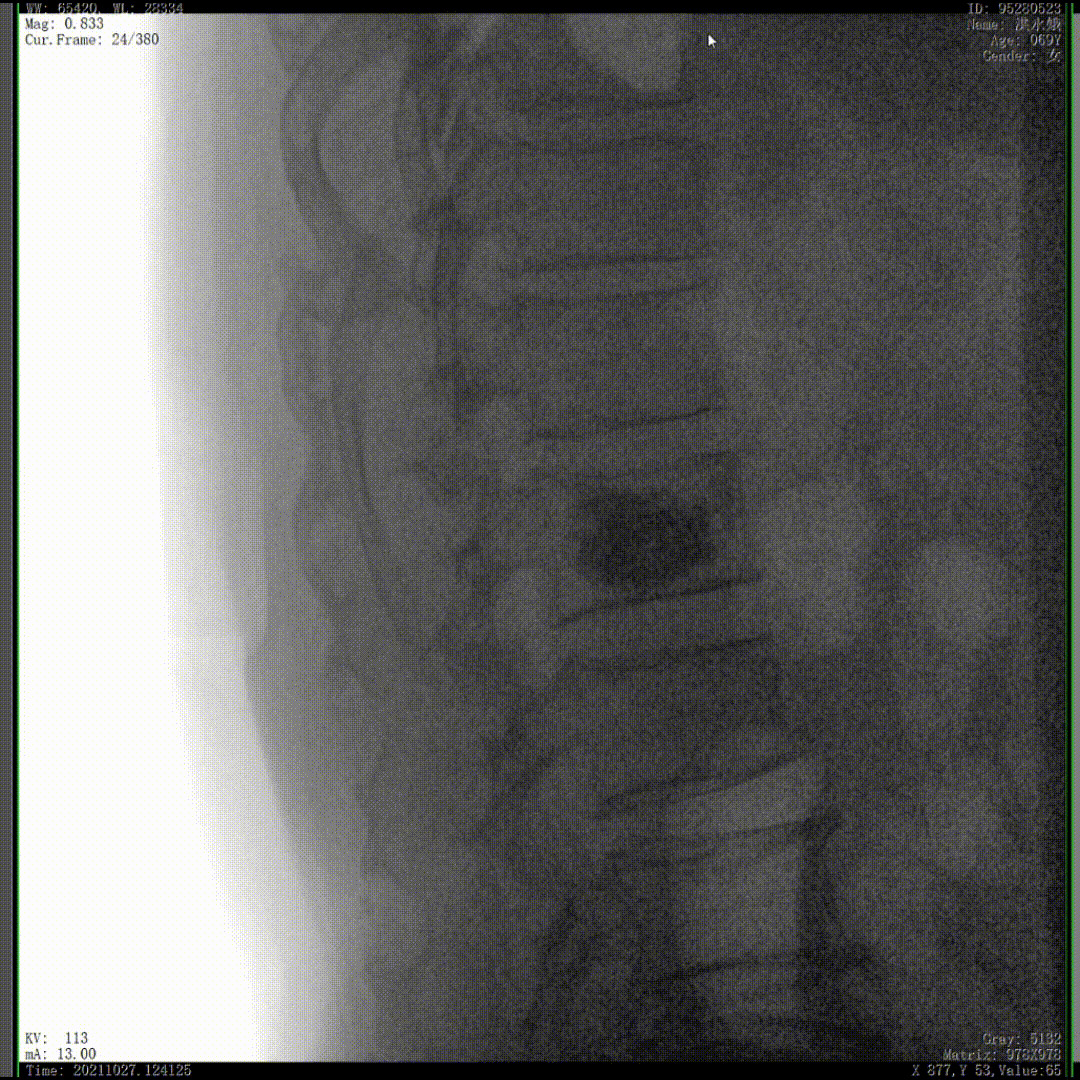

醫(yī)生通常會(huì)在“貓眼”里尋找進(jìn)針點(diǎn)和出針點(diǎn),憑醫(yī)生的經(jīng)驗(yàn)把釘子打在椎弓根里。手術(shù)比較依賴醫(yī)生的經(jīng)驗(yàn),萬(wàn)一出現(xiàn)偏差對(duì)病人來(lái)講就是毀滅性的打擊。如果在復(fù)雜的手術(shù)中有三維影像的支持,確保釘子精準(zhǔn)的打在椎弓根里,可大大的提高手術(shù)操作的精度。

“貓眼”指的是椎弓根在正位的投影。